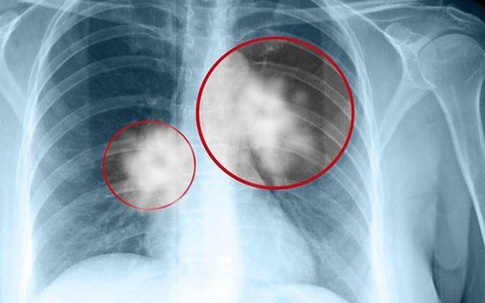

Trong 10 loại ung thư phổ biến thường gặp tại nước ta thì ung thư phổi xếp thứ nhất và là nguyên nhân gây tử vong hàng đầu. Vì thế, việc nhận biết những dấu hiệu ban đầu của căn bệnh ung thư phổi là vô cùng quan trọng.

Ung thư phổi là loại ung thư phổ biến nhất và cũng là ung thư gây tỷ lệ tử vong cao nhất trên toàn thế giới. Tại Mỹ mỗi năm có khoảng 174.000 người mắc mới và 160.000 người tử vong.